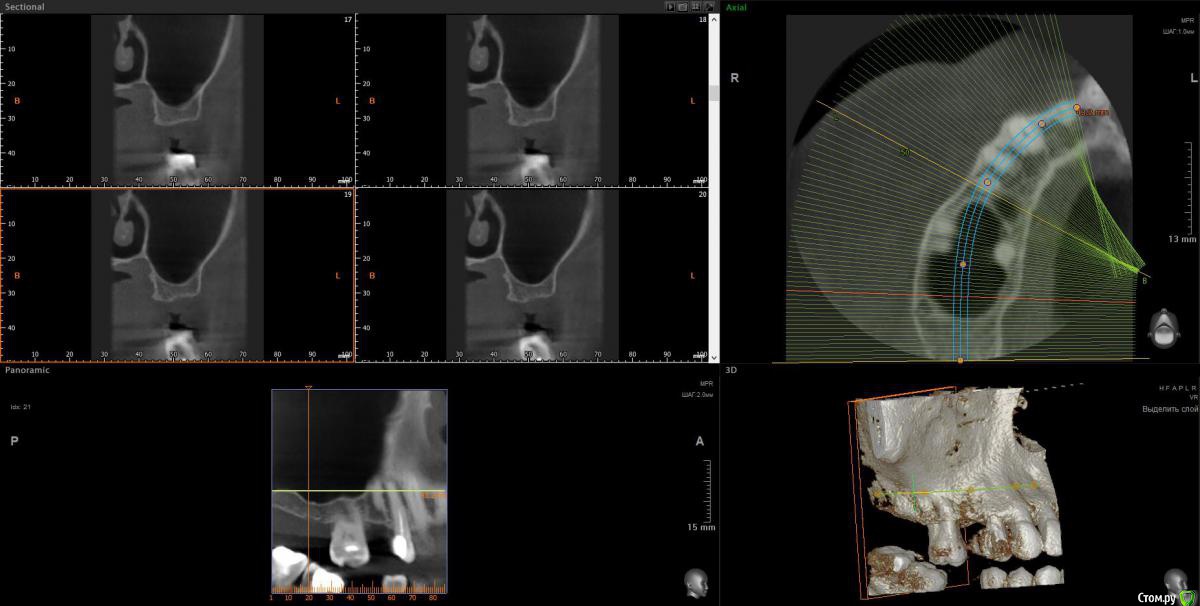

wladdX Опубликовано 11 мая, 2018 Поделиться Опубликовано 11 мая, 2018 Скриншоты зон 15 и 17 Ссылка на комментарий

Elena64 Опубликовано 11 мая, 2018 Автор Поделиться Опубликовано 11 мая, 2018 Скриншоты зон 15 и 1715.jpg15_1.jpg17.jpg17_1.jpgСкажите пожалуйста,а в зоне 7 зуба что не так?Вы отметили крестиками. Ссылка на комментарий

Elena64 Опубликовано 14 мая, 2018 Автор Поделиться Опубликовано 14 мая, 2018 Добрый вечер!Получила сегодня описание из Пикассо : 1.6 зуб. Коронковая часть: восстановлена нерентгеноконтрастной пломбой. Количество корней/каналов: три корня/четыре канала; На дистальной поверхности определяются твердые зубные отложения. В мезиально-щечном корне два канала. Периодонтальное пространство не расширено; Твердая пластинка альвеолы сохранена (Рис.2). В области отсутствующего 1.5 зуба — состояние после удаления. В лунке определяется фрагмент корня с ровным, четким контуром, раз- мерами 3.5х2,4х8,8 мм. Периодонтальное пространство не прослеживается.ДИАГНОСТИЧЕСКОЕ ЗАКЛЮЧЕНИЕ: Частичное отсутствие зубов. Фрагмент корня в лунке отсутствующего 1.5 зуба. Ссылка на комментарий